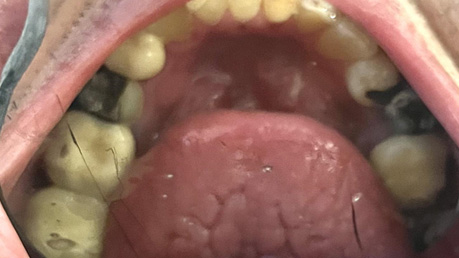

Patient Intraoral Photographs

- Maxilla

Dental Hygiene: The patient has osteoarthritis and cannot perform oral hygiene on himself. At the first appointment, he revealed he has a PSW that brushes for him using a manual toothbrush with Crest toothpaste 0.454% Stannous fluoride (1100 ppm fluoride) twice daily (morning before breakfast and before bedtime). No other fluoridated products are used at home. He consumes fluoridated tap water and does not use mouthwash. Fluoride varnish has been applied to his teeth at scaling and root planing (SRP) appointments. Currently, he has only been getting SRP once a year as a preventative procedure. His latest SRP was in October 2023 when I first saw the patient. During his last SRP appointment, there was heavy generalized plaque and supragingival calculus, moderate generalized subgingival calculus, and bleeding on probing (BOP) localized to the mandibular anterior teeth. The gingiva was red and inflamed throughout the mouth. The interproximal areas and gingival third of the teeth were often missed during his at-home oral hygiene regimen. The patient states the PSW brushes with horizontal strokes for less than 30 seconds each day. The patient states that he gets flossed every other day or every 3-4 days, but this did not correspond to what was seen clinically. He appeared motivated to attain better oral hygiene, but he states his PSW is not motivated to brush his teeth for longer durations and is reluctant to provide him with oral hygiene (OH) unless he requests for it daily. The patient has no family history of oral cancer, has never smoked, does not consume alcohol, does not use chewing tobacco, and does not excessively expose himself to the sun.

Carious Lesions: 12MV, 13DV, 14MOV, 25O, 31V, 42MV, 45V

Missing: 18, 24, 25, 26, 28, 37